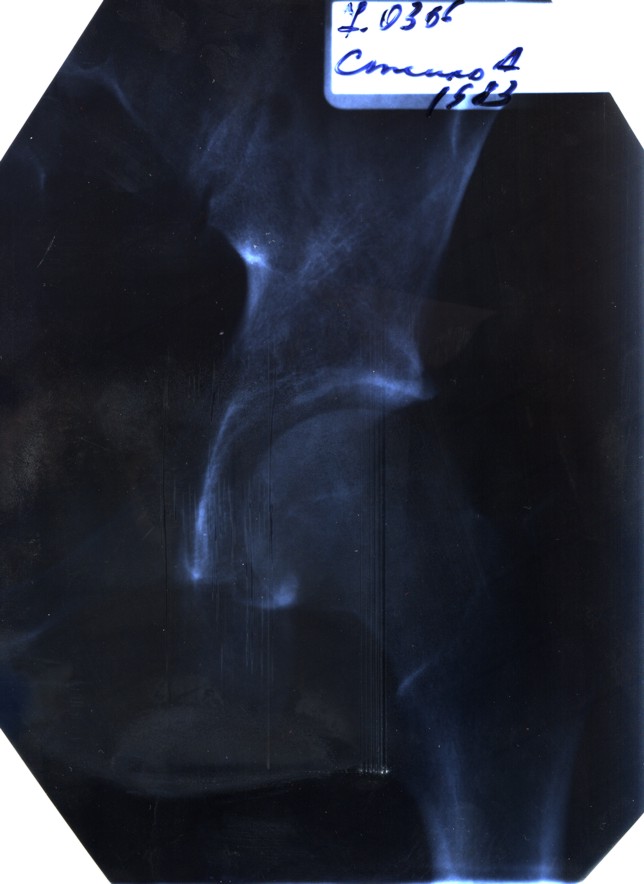

В понедельник 6.03.06 проснулся утром от боли в тазобедренном суставе. Хотя в воскресенье небыло никаких признаков. Пошел в поликлинику. Поставили диагноз коксоартроз левого тазобедренного сустава 1-ой степени. Через день боль стихла а через 2 прошла совсем. Я занимаюсь бодибилдингом. Могло ли это произойти от нагрузки? Какие последствия? Лечение? Возможно ли продолжать заниматься уменьшив нагрузку на ноги, или совсем ее исключить?

Никакх катастроф на снике не видно. На период обострения боли желательно снизить нагрузку на ногу, то есть передачу массы тела через сустав. Поменьше ходить, безать, носить тяжести. Заниматься можно, но упражнения выбирать с учетом этого органичения.

Ртг - темно и мрачно, но сдается, что опорная поверхность с центральным вдавлением.Это признак перегрузки сустава, продумайте свой комплекс упражнений - никаких приседаний со штангой и фанатизма с отягощениями стоя. Занимайтесь лучще плаванием :-).